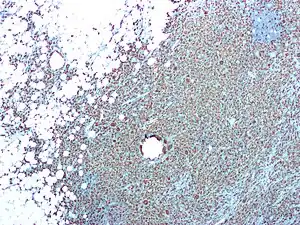

| CD68 immunostaining on this photomicrograph shows macrophages and giant cells in a case of xanthogranulomatous pyelonephritis | |

Xanthogranulomatous pyelonephritis

Xanthogranulomatous pyelonephritis is an unusual form of chronic pyelonephritis characterized by granulomatous abscess formation, severe kidney destruction, and a clinical picture that may resemble renal cell carcinoma and other inflammatory kidney parenchymal diseases. Most affected individuals present with recurrent fevers and urosepsis, anemia, and a painful kidney mass. Other common manifestations include kidney stones and loss of function of the affected kidney. Bacterial cultures of kidney tissue are almost always positive.[25] Microscopically, there are granulomas and lipid-laden macrophages (hence the term xantho-, which means yellow in ancient Greek). It is found in roughly 20% of specimens from surgically managed cases of pyelonephritis.[10]